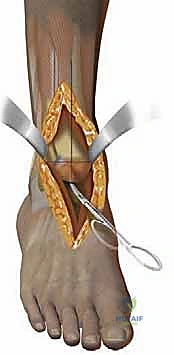

هدفنا الأسمى في هذا الإجراء، كما هو الحال دائماً في كل تدخل جراحي، هو التنفيذ الميكرو-جراحي الدقيق للوصول إلى التموضع المثالي للمكونات الصناعية، وتحقيق تثبيت أولي صلب، وهو حجر الزاوية لنجاح "التثبيت البيولوجي الثانوي" (حيث ينمو العظم الطبيعي داخل مسام المفصل الصناعي) والذي نعتمد عليه لتحقيق نتائج مستدامة مدى الحياة.

* التثبيت: هو مفصل "غير إسمنتي". يتم تغطية الأسطح المعدنية الملامسة للعظم بطبقة مسامية من التيتانيوم وهيدروكسي أباتيت (Hydroxyapatite). هذه الطبقة تشجع العظم الطبيعي للمريض على النمو داخل مسام المفصل (Bone Ingrowth)، مما يوفر تثبيتاً بيولوجياً صلباً يدوم لسنوات طويلة.

* التصميم الميكانيكي: يشارك هذا النظام نفس الهندسة التشريحية الممتازة للمكونات المعدنية لنظام سالتو، ولكن مع اختلاف جوهري واحد: المكون البلاستيكي (البولي إيثيلين) هنا ثابت (Fixed-bearing) ويتم قفله بإحكام داخل المكون المعدني العلوي (الظنبوبي).